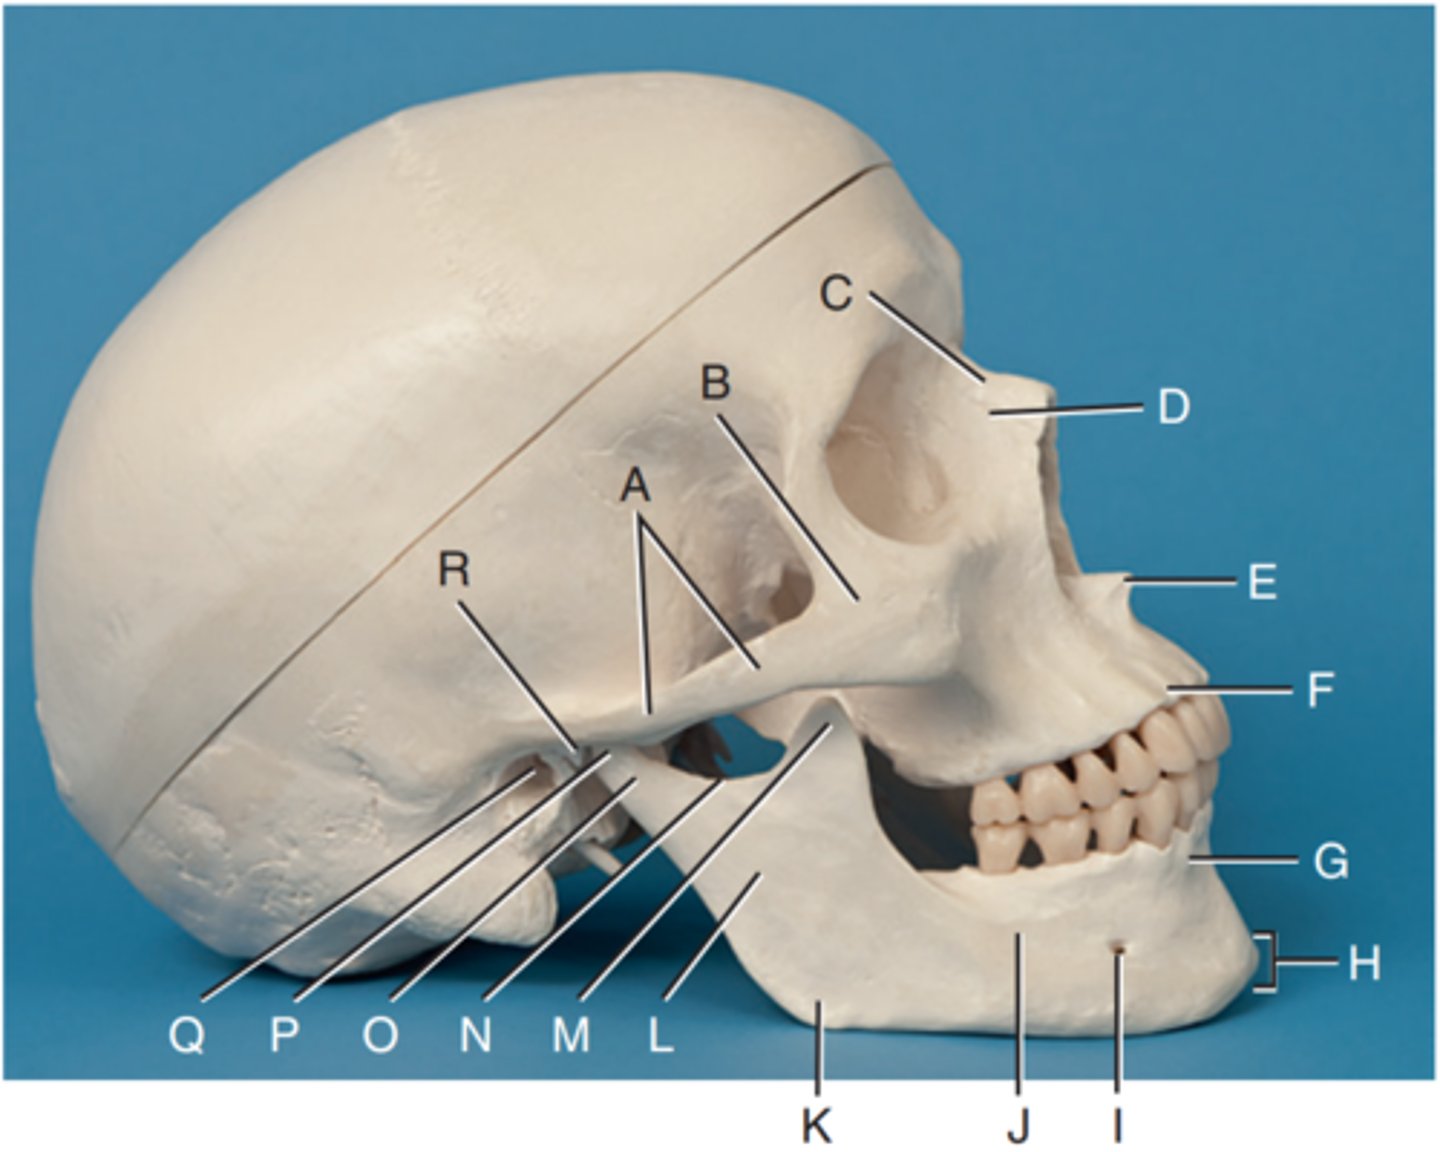

Zygomatic arch

Label A

Right zygomatic bone

Label B

Right nasal bone

Label C

Frontal process of right maxilla

Label D

Anterior nasal spine

Label E

Alveolar process of maxilla

Label F

Alveolar process of mandible

Label G

Mentum or mental protuberance

Label H

Mental foramen

Label I

Body of mandible

Label J

Angle (gonion)

Label K

Ramus of mandible

Label L

Coronoid process

Label M

Mandibular notch

Label N

Neck of mandibular condyle

Label o

Condyle or head of mandible

Label P

EAM

Label Q

TM fossa of temporal bone

Label R